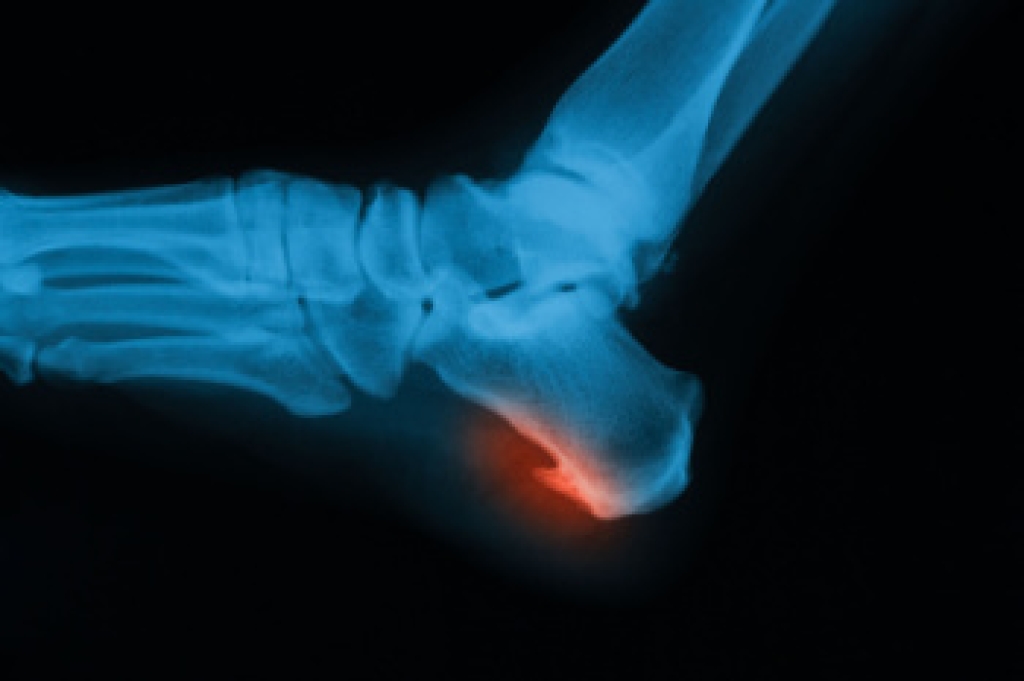

Plantar fasciitis is a common cause of heel pain that occurs when the thick band of tissue connecting the heel to the toes becomes inflamed. This is often due to overuse, improper footwear, obesity, or high-impact activities, such as running or jumping. The heel may look normal from the outside, but it can be tender to the touch and feel swollen in severe cases. Many individuals describe a sharp, stabbing pain with the first steps in the morning or after prolonged sitting, which can ease slightly with activity but worsen later in the day. Plantar fasciitis affects nearly 10 percent of the population at some point in their lives, making it one of the most common foot disorders. A podiatrist can diagnose the condition through a physical examination and gait analysis. Treatment may include stretching exercises, orthotics, supportive footwear, anti-inflammatory therapies, or advanced interventions for chronic cases. Early professional care helps reduce pain and prevent long-term complications. If you experience persistent heel discomfort, it is suggested that you make an appointment with a podiatrist.

Plantar fasciitis is the inflammation of the thick band of tissue that runs along the bottom of your foot, known as the plantar fascia, and causes mild to severe heel pain.